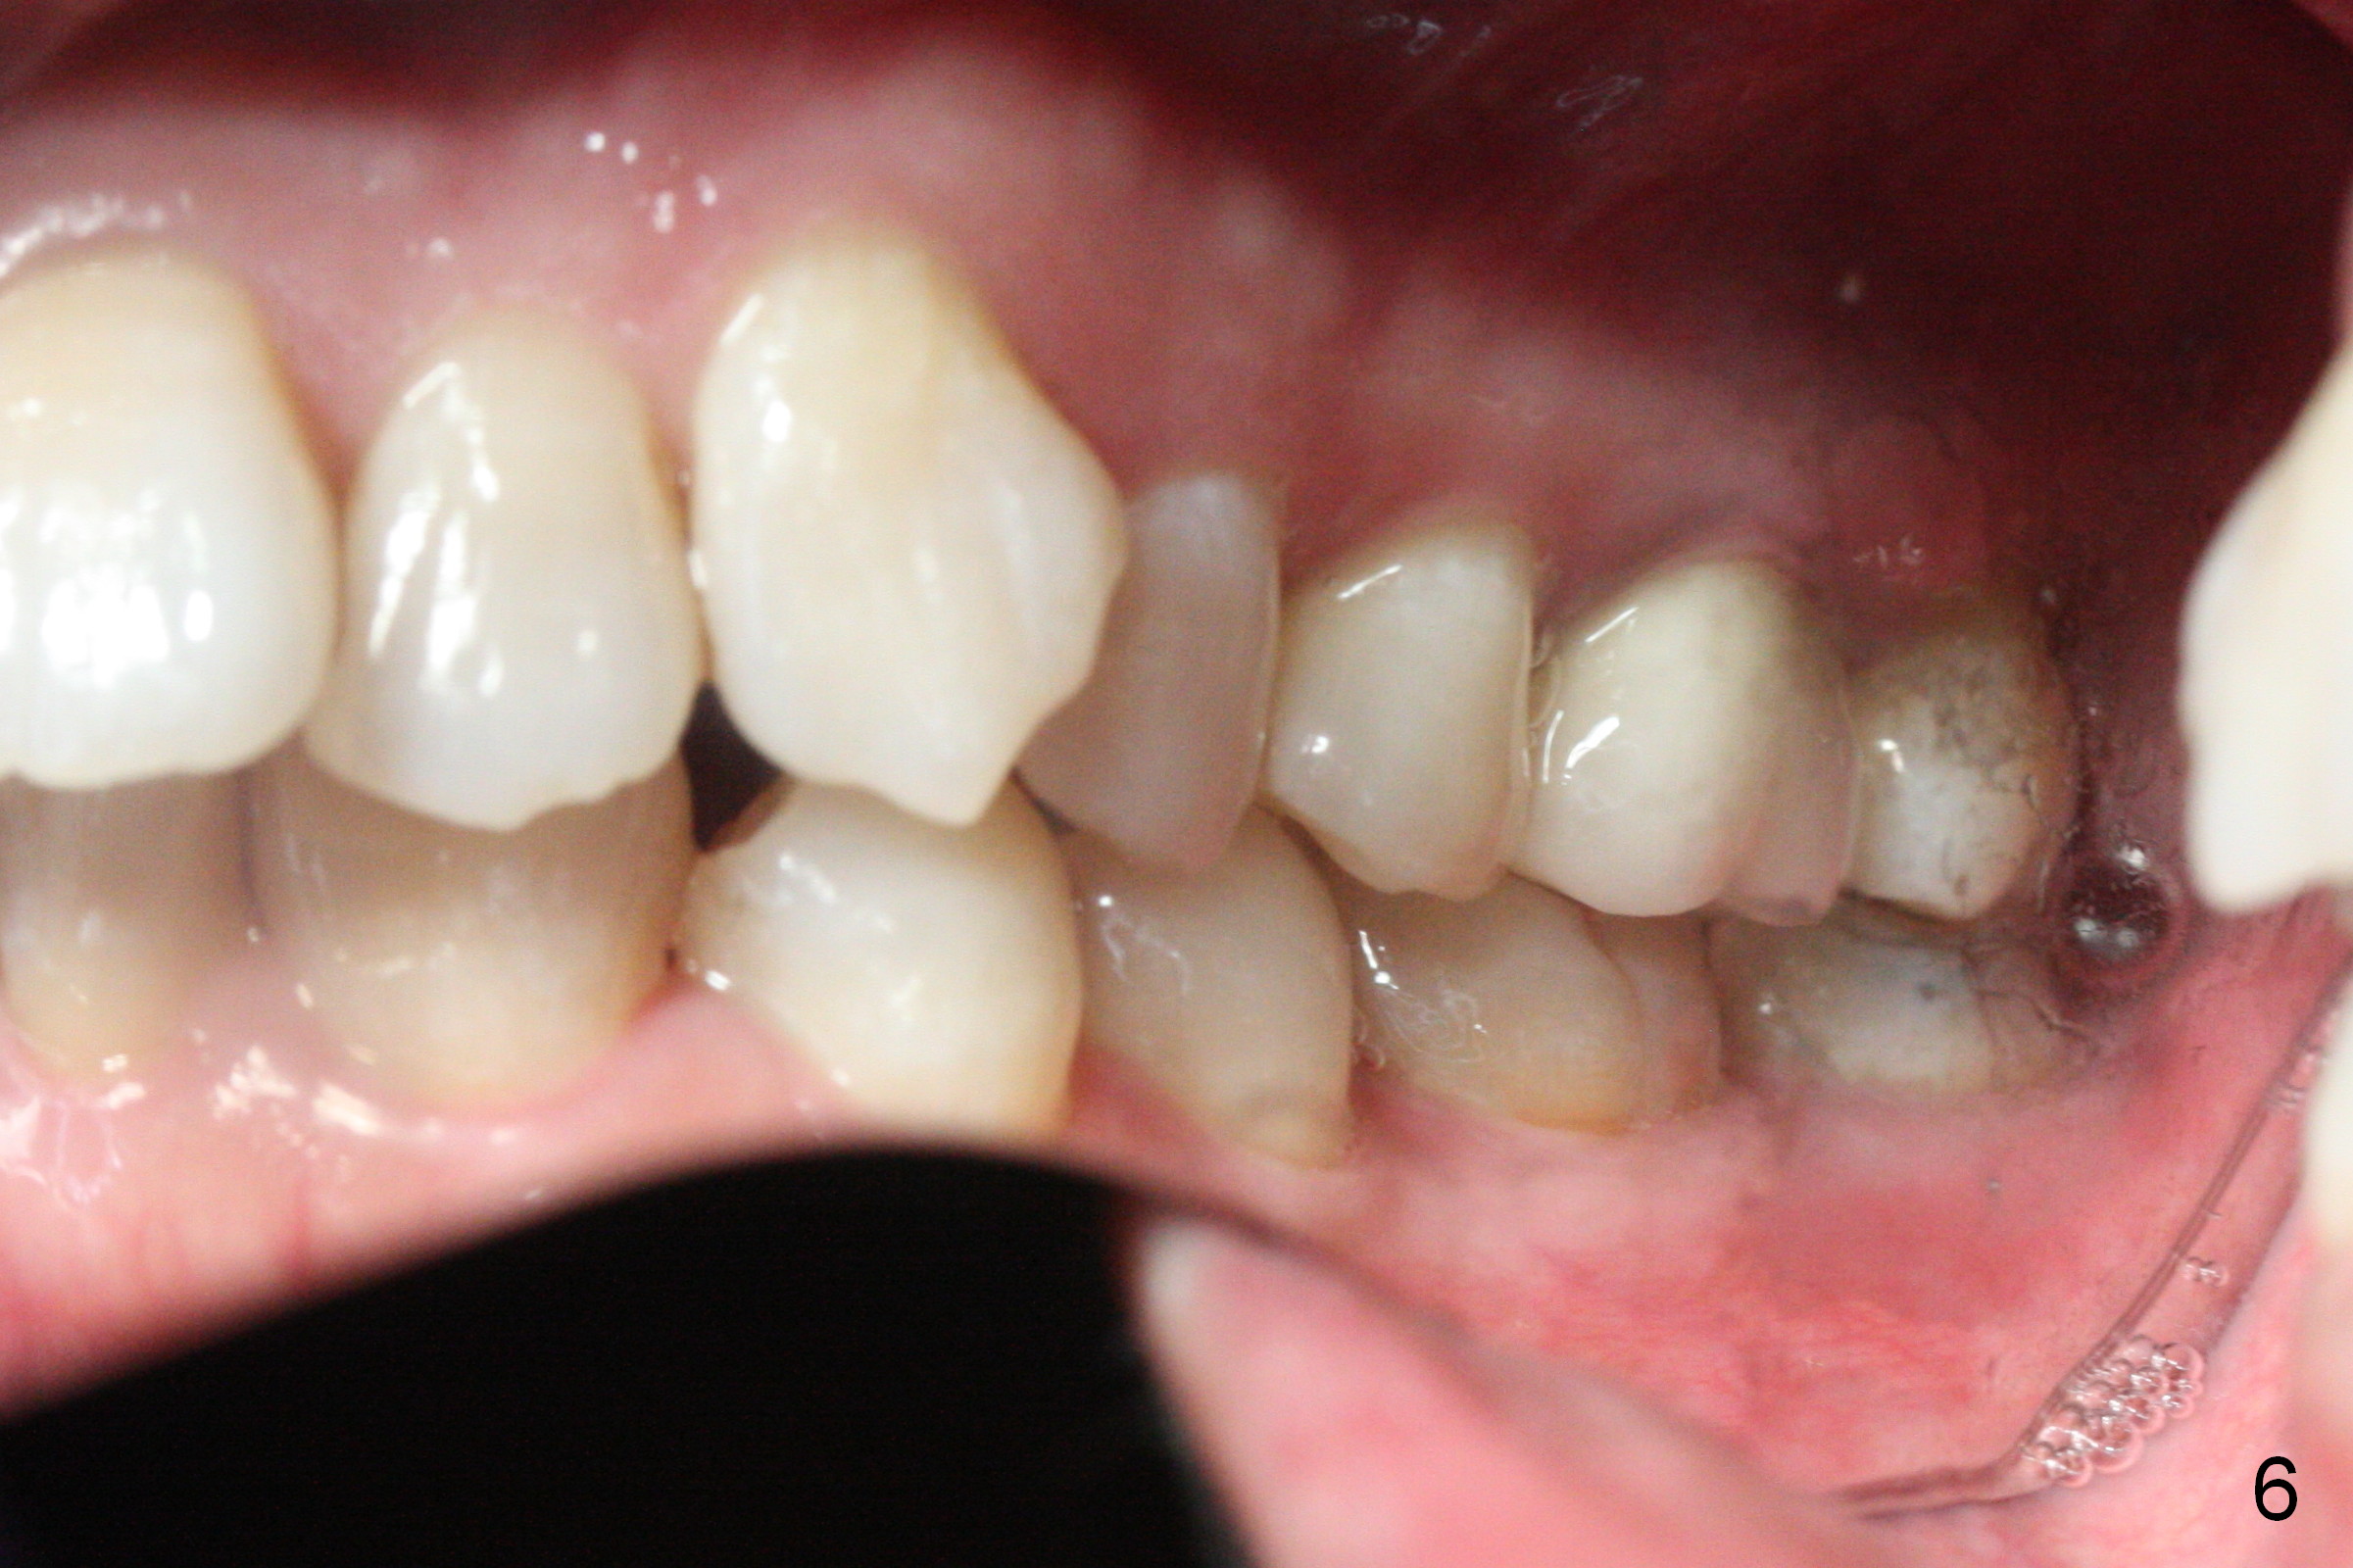

A 41-year-old woman requests orthodontic treatment because of the upper blocked out canines (Fig.6,8). Her facial and dental midlines coincide (Fig.1). Her profile is slightly convex (Fig.2,3) with increase in overjet (Fig.4). Orthodontic treatment includes extraction of U4s and placement of 2 mini-implants between U5 and 6 (Fig.5 o) when arch wires change to 18x25. Power arms (as high as possible) are placed between U2 and 3. U1-3s are retracted at the same time (en mass) because of absolute anchorage of the mini-implants. Retraction time will be reduced. Interproximal reduction (IPR) will be done especially at LR3 (macrodontia, Fig.5) if the lower arch turns out to be too large.

Eight months post banding, UR3 appears to be distalized with de-rotation (Fig.26), while UL3 is slightly over-distalized with mesial space (Fig.27 arrow). LL5 remains rotated (Fig.28). One months later, anterior over bite and over jet seem to be normal. In spite of lack of Class I anterior occlusion, it is decided that the upper posterior teeth should be mesialized. Next visit, wires will be changed to 16x16 with ligature wire between U3-3 and power chains between U3 and 5.